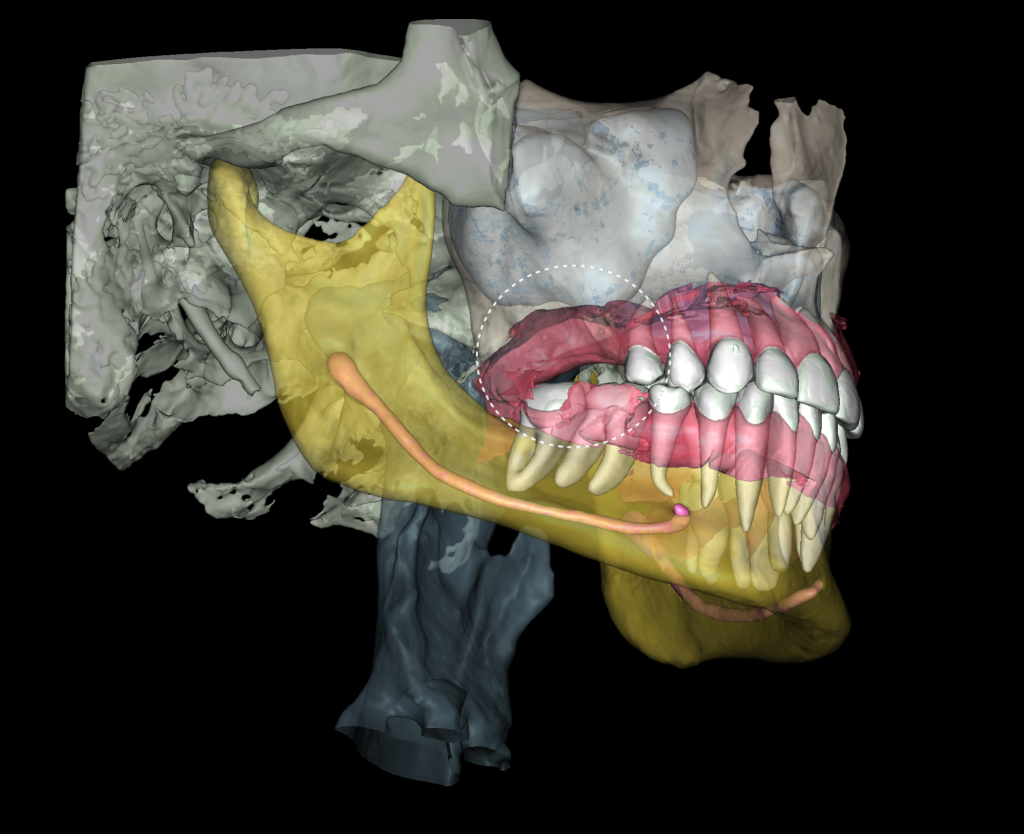

The “STL” module enables the creation of virtual models for guided implant surgery. This is achieved by loading intraoral scan data into the module and selecting a suitable CBCT for merging

The slide illustrates the sequence of stages involved in prosthetic rehabilitation, obtaining digital impressions and uploading them to the Diagnocat STL module, to creating temporary crowns and forming the desired emergence profiles for implants

The slide demonstrates the continuation of prosthetic treatment on the lower jaw